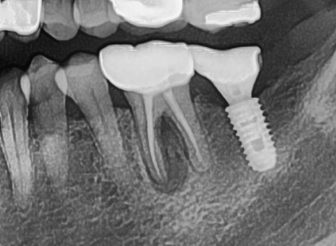

치근단 농양을 가진 환자분이 내원 하였습니다.

치근단 농양으로 가득찬 hopeless 치아

수 년 전, 충치로 인한 큰 감염으로 인하여 신경치료를 받은 치아 이지만

재 감염으로 인해 골 내부에 염증이 퍼져서

증상이 없이 감염이 발생하고 있습니다.